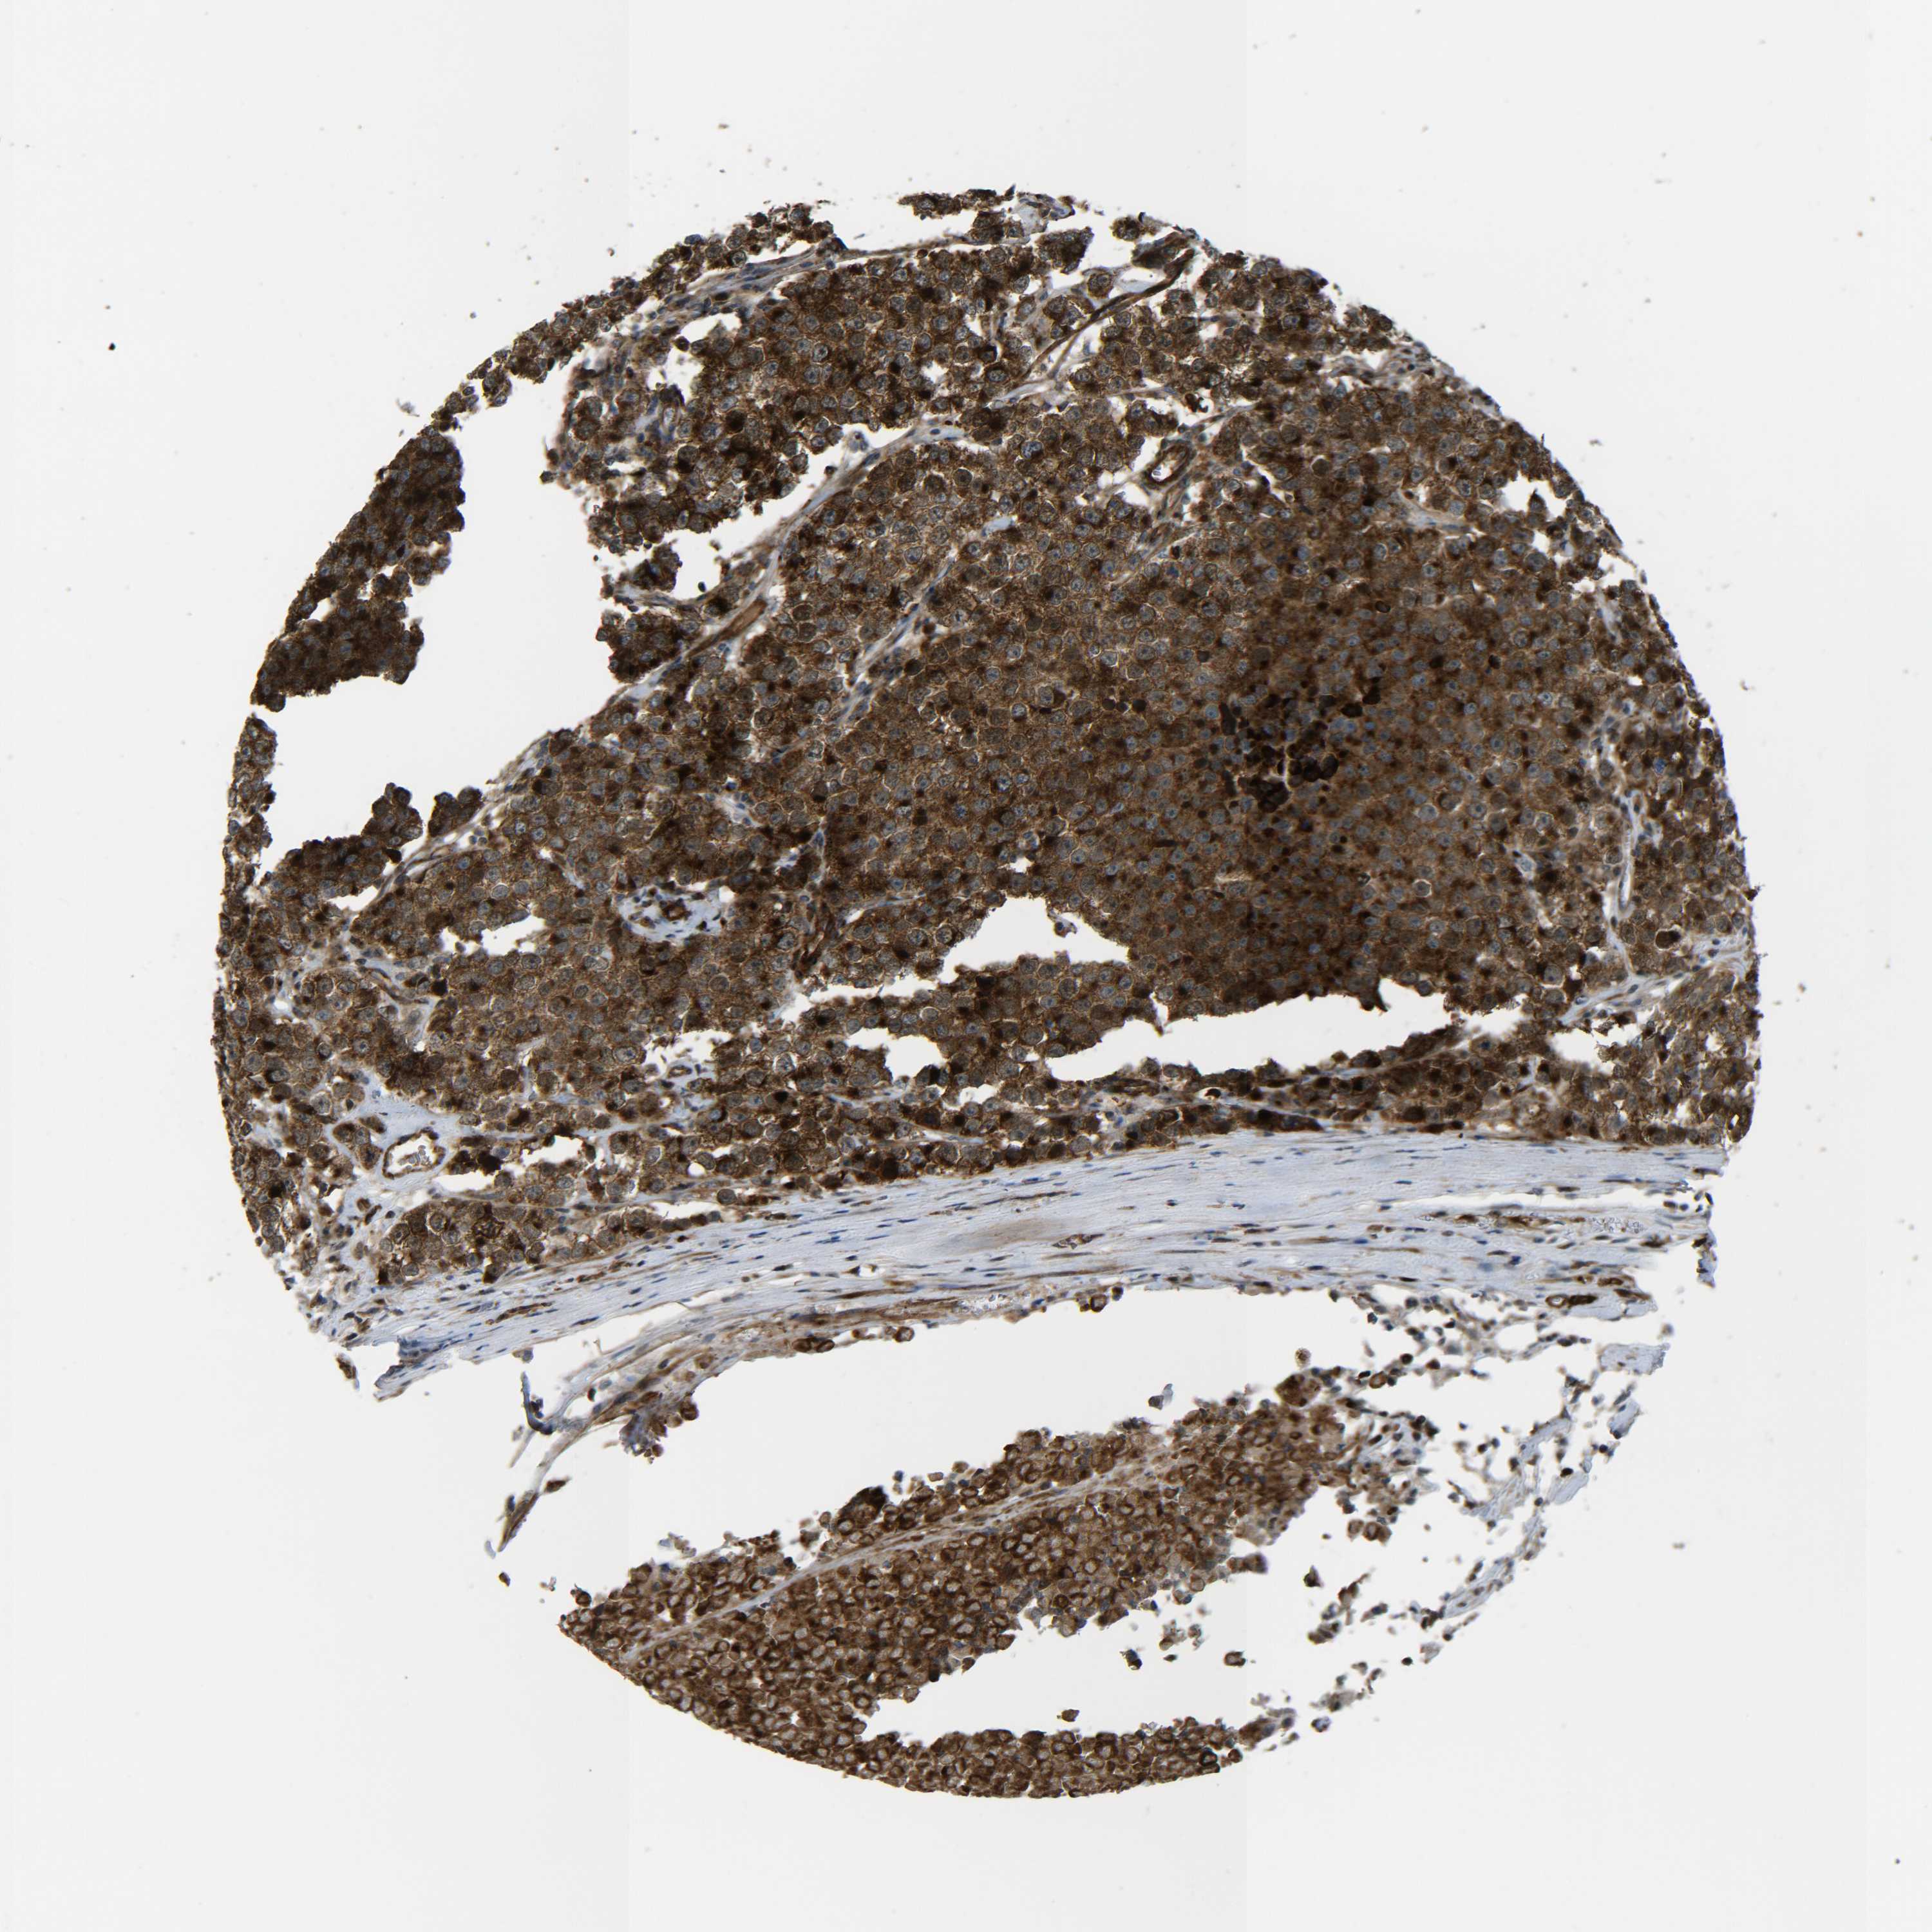

TESTIS CANCER - Protein expressioni

A mouse-over function shows sample information and annotation data. Click on an image to view it in a full screen mode. Samples can be filtered based on level of antibody staining by selecting one or several of the following categories: high, medium, low and not detected. The assay and annotation is described here.

Note that samples used for immunohistochemistry by the Human Protein Atlas do not correspond to samples in the TCGA dataset.

Antibody stainingi

Antibody staining in the annotated cell types in the current human tissue is reported as not detected, low, medium, or high, based on conventional immunohistochemistry profiling in selected tissues. This score is based on the combination of the staining intensity and fraction of stained cells.

Each image is clickable and will lead to virtual microscopy that enables deeper exploration of all samples and also displays staining intensity scores, fraction scores and subcellular localization as well as patient and tissue information for each sample.

Antibody HPA001490

Antibody HPA013616

Staining

High

Medium

Low

Not detected

Intensity

Strong

Moderate

Weak

Negative

Quantity

>75%

75%-25%

<25%

None

Location

Nuclear

Cytoplasmic/membranous

Cytoplasmic/membranous,nuclear

Carcinoma, Embryonal, NOS

Seminoma, NOS